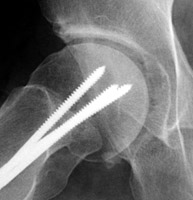

One radiograph of the shoulder (A), and one of the hip (B), both with a crescent of air-density within the joint adjacent to the head of the humerus and femur respectively. The pneumoarthrogram sign is simply the finding of gas-density within the joint and signifies that no joint effusion is present. It is a reliable sign and of great value when identified.

AP Shoulder - Click on the image for a larger versionAFrog lateral hip - Click on the image for a larger versionB